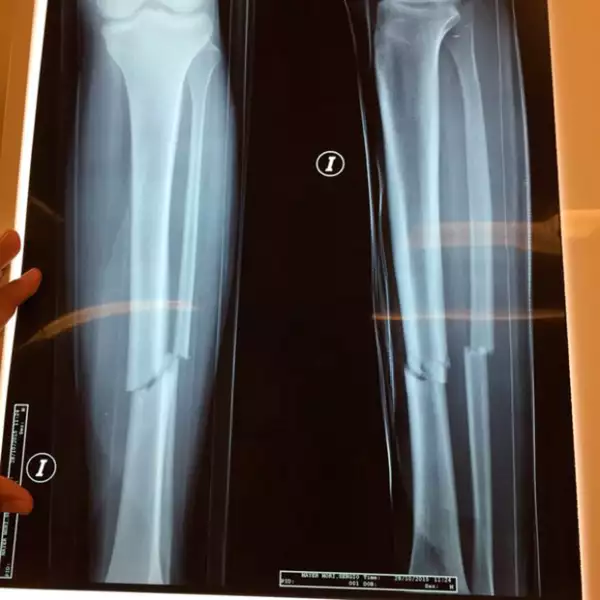

Sergio Mayer Mori sufrió un accidente en motocicleta la semana pasada en Cholula, Puebla, la cual le originó una fractura de tibia y peroné.

Horas más tarde, el propio Sergio Mayer publicó que su hijo fue intervenido: "Gracias a los que han preguntado del estado de @SMayerMori , ayer entró a cirugía por la fractura de tibia y peroné y está en recuperación (...) Salió todo muy bien gracias a Dios, mil bendiciones por sus deseos y comentarios hacia @SMayerMori".

"Me pusieron cinco clavos, uno va desde la rodillas por todo el hueso, por la médula, hasta el talón", declaró Sergio Mayer Mori a Televisa Espectáculos.